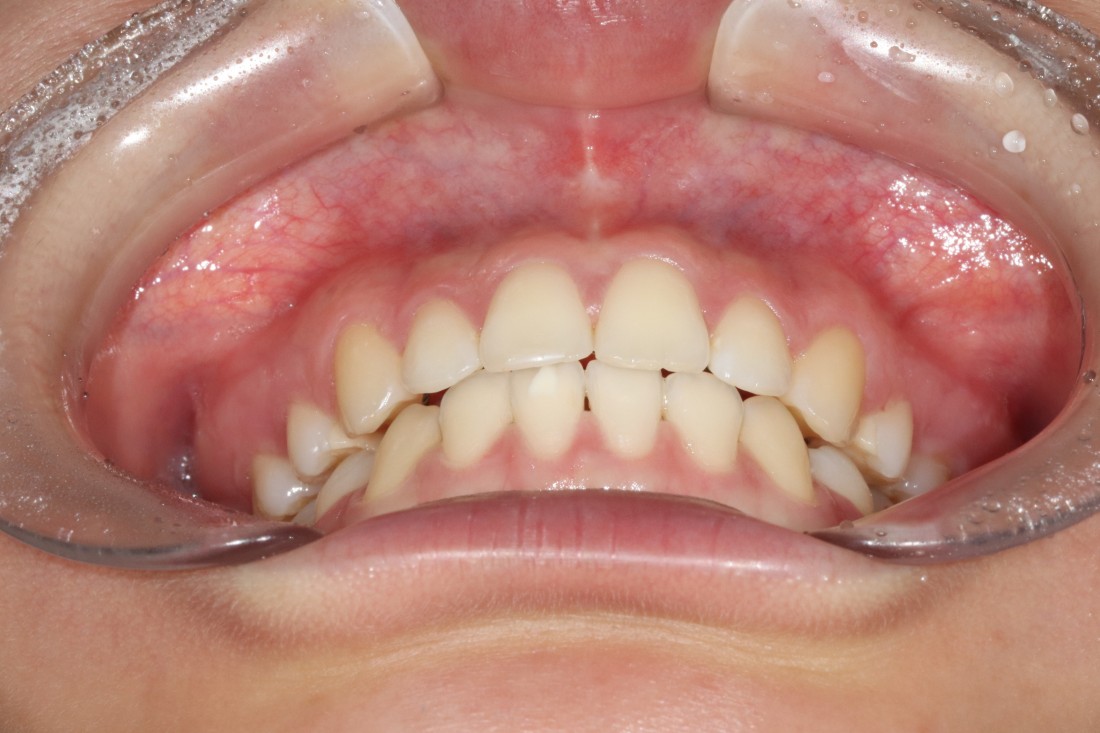

발치교정, 비발치교정을 결정하는 것은

교정 전 3차원 105항목 정밀검사를 통해

교정전문의 대표원장님과의

세심한 상담을 통해 정하게 됩니다.

무조건 비발치 교정만이 좋은 것은 아니며,

개인차에 의해 발치교정이 필요한 경우에는

발치교정을 통해 원하는 교정치료 결과를

얻을 수 있습니다.